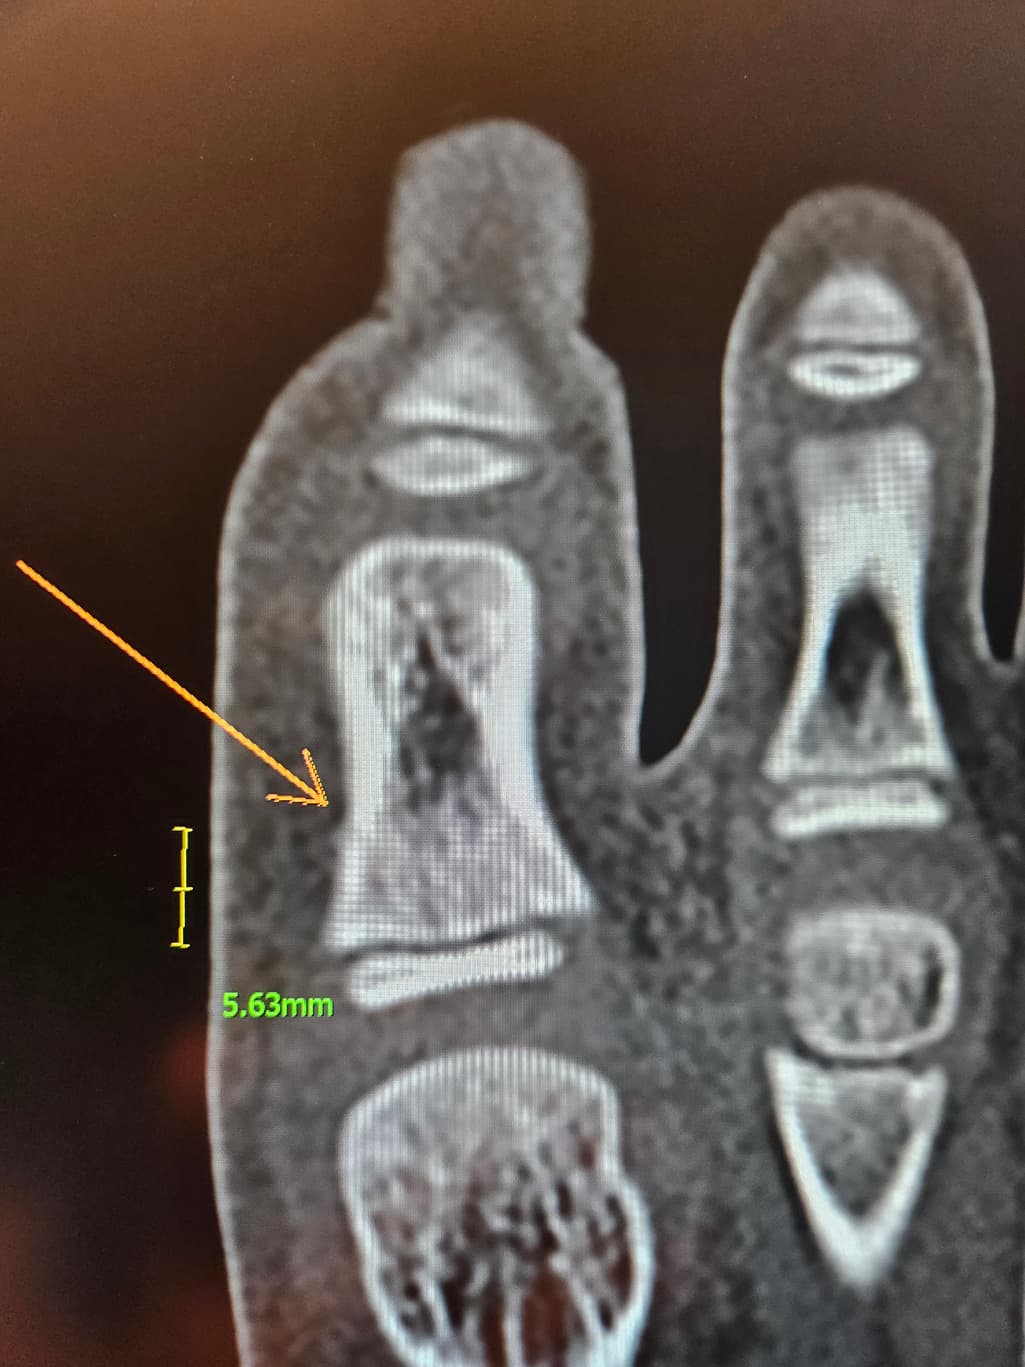

첫번째 사진은 엑스레이

두번째 세번째는 ct입니다

수술하자하는데 제가 일주일만 경과보고프다해서 일단 통깁스만했는데ㅠ

핀 수술이 필요할까요?ㅠ

아동의 경우 뼈 성장판에 영향을 줄 수 있는 부상이 있을 수 있습니다. 통깁스를 한 후 일주일 정도 경과를 지켜보는 것은 좋은 접근입니다. 그러나 통증이 지속되거나 상태가 악화된다면, 수술적 치료가 필요할 수 있습니다.

전문의와 상담하여 최선의 치료 방법을 결정하는 것이 중요합니다!